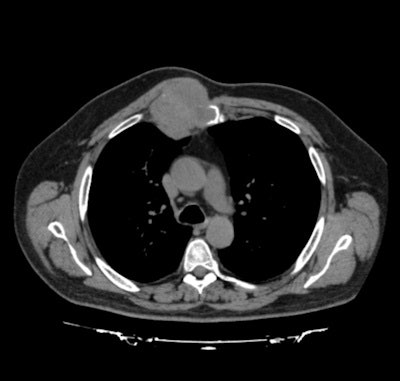

The patient presented with a painful 8 x 8-cm right parasternal mass. A 3D perfusion CT showed involvement of both pectoral muscles, as well as the sternal body and the third and fourth bilateral ribs, with no other distant metastases. The findings suggested primary sternal chondrosarcoma, wrote Aranda and colleagues Dr. Marcelo F. Jiménez, PhD, María Rodríguez, and Dr. Gonzalo Varela, PhD, from Salamanca University Hospital in Salamanca, Spain.

The authors created a 3D surface rendering of the chest wall and tumor to confirm resection margins and apply them to create the prosthesis extent for reconstruction. Next, they transmitted the high-resolution 3D CT perfusion DICOM data to Australia via Anatomics proprietary software. Anatomics then used the data to create a 3D reconstruction of the chest wall and tumor.